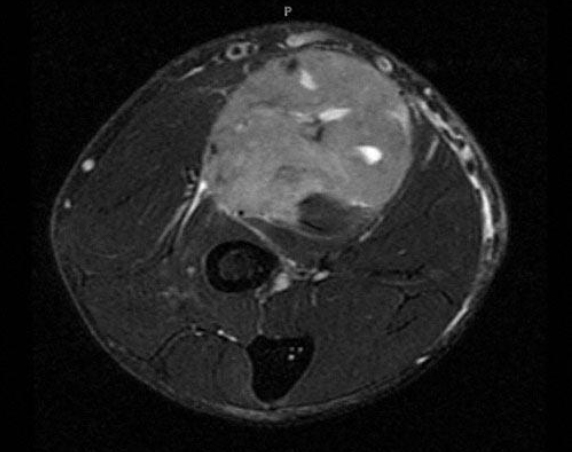

A 45-year-old man has a mass in the left volar forearm. An MRI is shown. Oncologic resection will involve removing all muscles of the anterior forearm compartment. Which of the following techniques is most appropriate to reconstruct finger flexion postoperatively?

The correct response is Option C.

A free gracilis muscle would provide a good strength and excursion match to the native finger flexors it would replace. Vascular and nerve connections could be performed in the distal upper arm, outside of the zone of resection. While individual finger flexion would not be restored, the patient would be able to make a composite fist after this surgery.